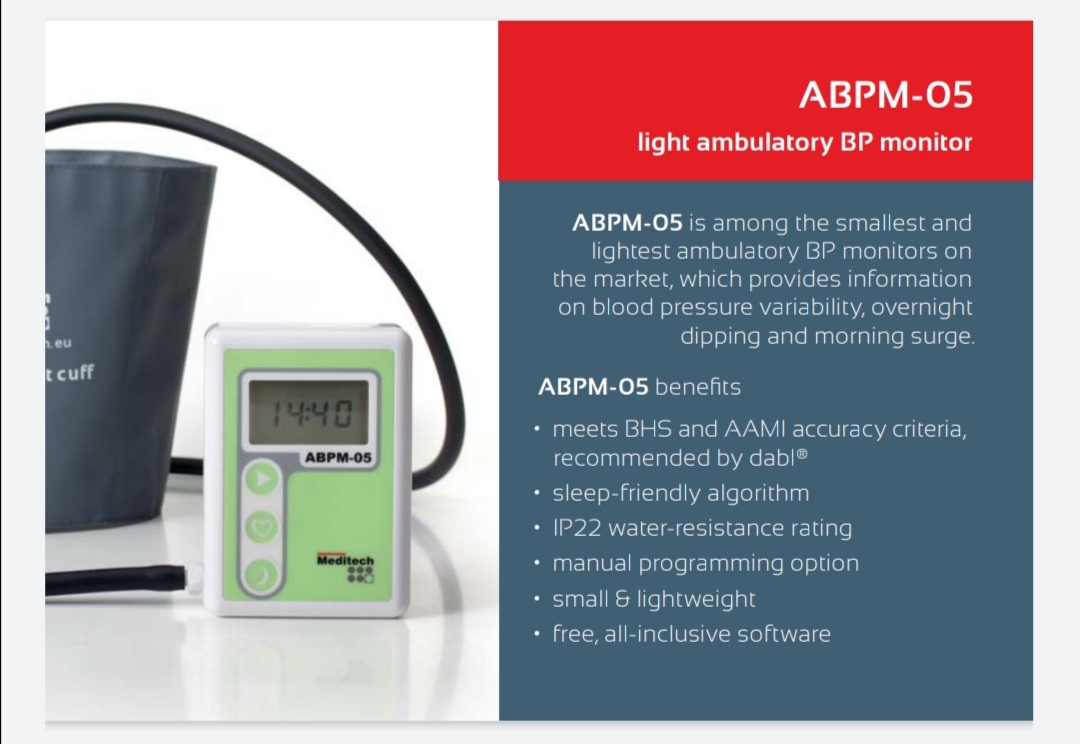

Meditech ABPM-06

ABPM Meditech,Hungary